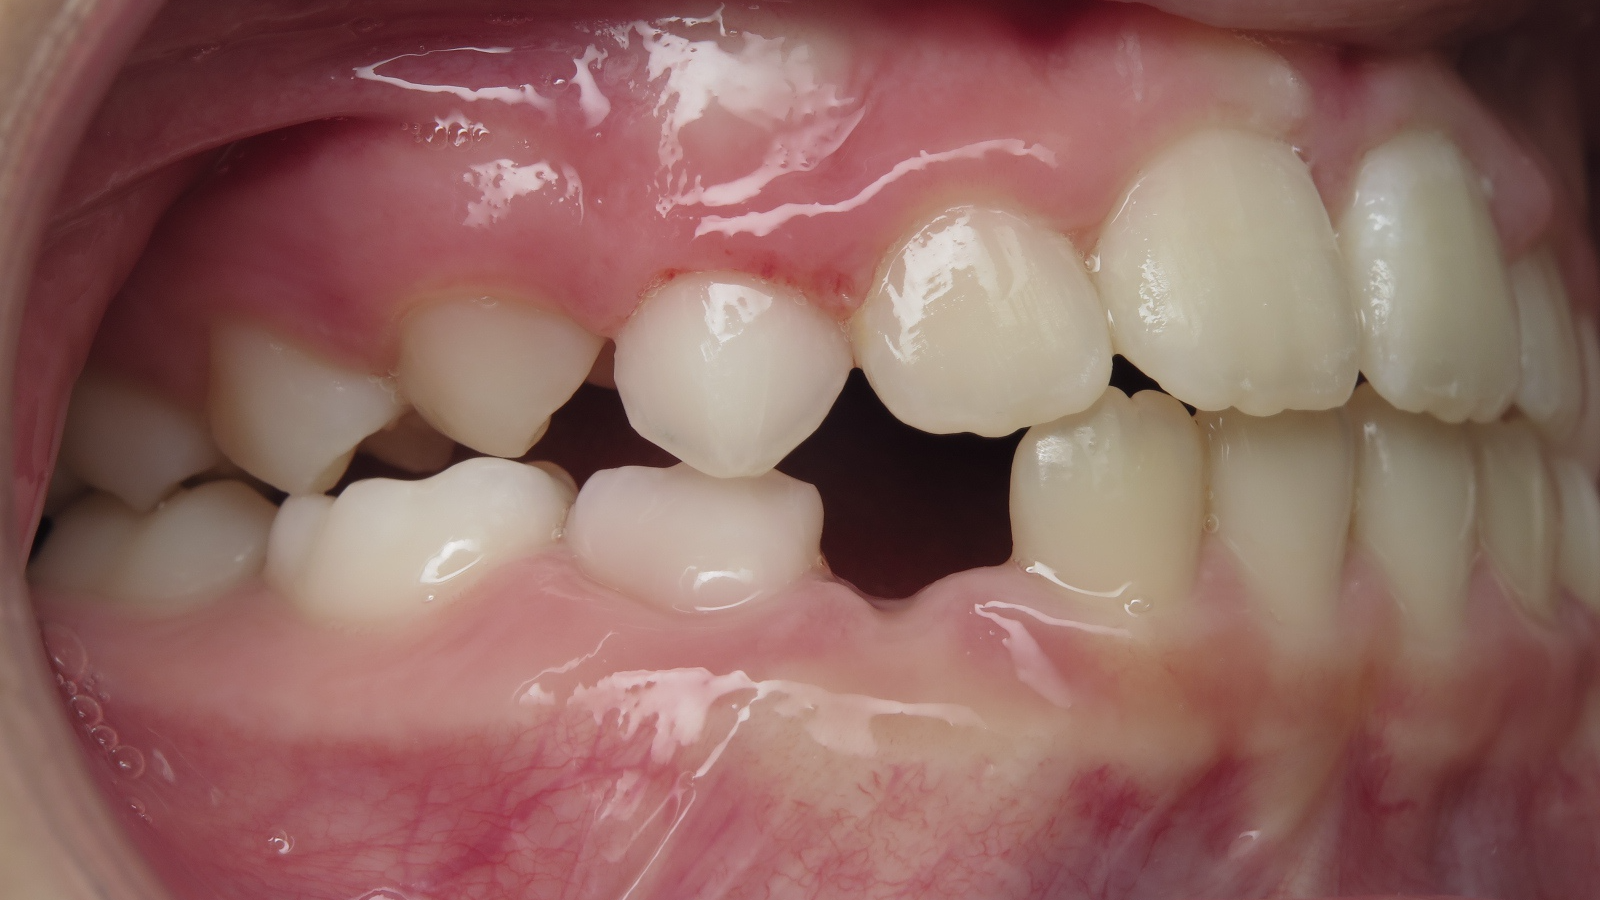

appareillage mobile pendant 22 mois

bilan début et en cours de traitement